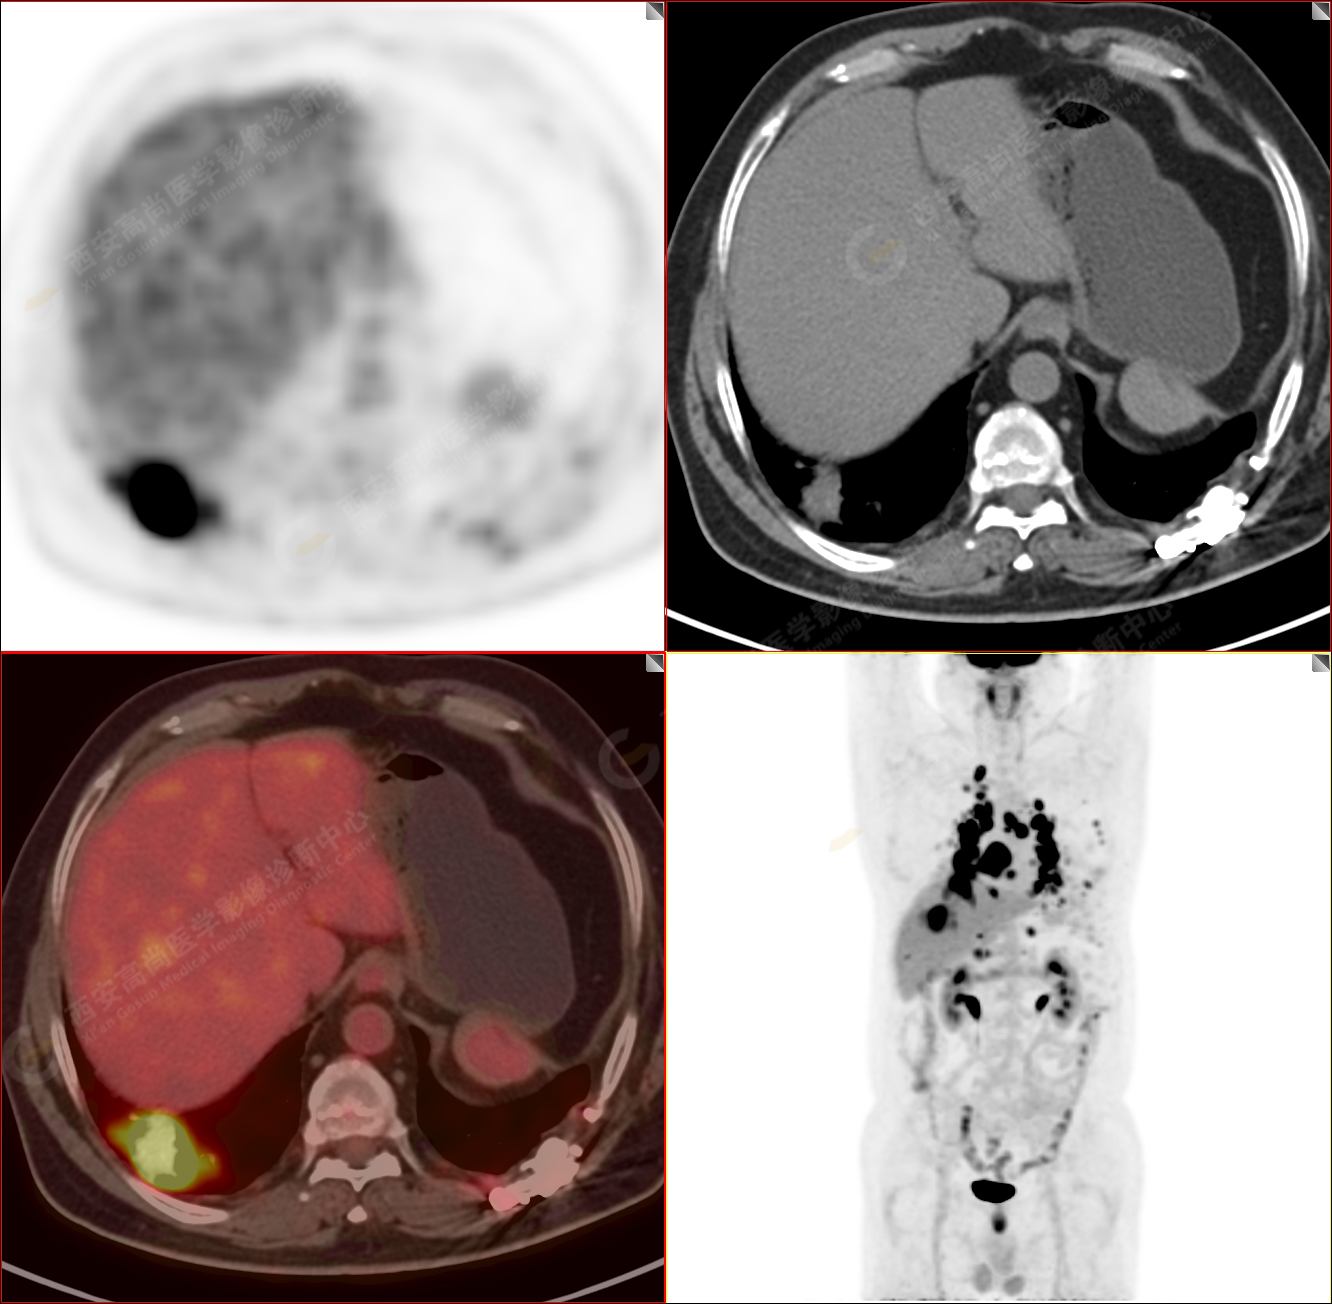

PET/CT-MR診斷結(jié)節(jié)病雙肺及全身多發(fā)淋巴結(jié)廣泛累及1例【西安高尚病例】

男性,53歲,頭暈半月入院,CT發(fā)現(xiàn)肺內(nèi)腫塊,雙肺多發(fā)大小不等實(shí)性及粟粒樣結(jié)節(jié),雙肺門(mén)及縱隔多發(fā)腫大淋巴結(jié)。病程中無(wú)發(fā)熱、胸悶氣及胸部不適。既往:左側(cè)肋骨外傷史。

PET-MR圖像